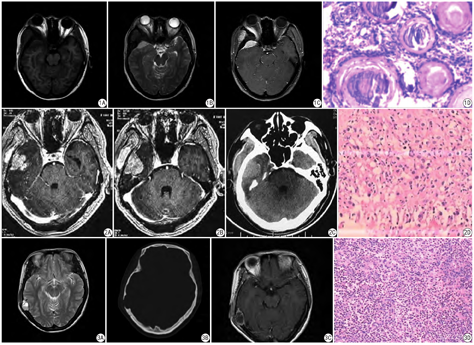

7例侵袭性脑膜瘤CT表现为颅板骨质破坏不一,颅骨增生硬化改变,2例骨质明显破坏,可见残留骨或钙化灶,颅内外板边缘不光整,周围可见较大软组织肿块,MR呈等T1、偏高T2信号,边界多较清,增强检查均有较明显强化,并有脑膜尾征(图1)。8例转移瘤,4例颅骨溶骨性骨破坏,范围较大,2例呈虫蚀状骨质破坏,破坏较小,无硬化边,边缘不清;周围均可见较大软组织肿块,呈稍长T1长T2信号影,增强呈中等强化;1例可见结节样强化(图2),1例累及颈静脉孔。6例嗜酸性肉芽肿CT表现为颅骨局部缺损,由稍高密度软组织肿块代替,范围较小,呈边缘整齐的穿凿样骨破坏,周边可见轻度硬化,膨胀不明显,见"双边征"(颅骨内外板破坏范围不一致)(图3),1例见斑点状死骨,MR病灶呈现长T1长T2信号,增强明显强化,3例见脑膜尾征,1例见结节环形强化,1例周围脑组织大片水肿灶,2例为2个病灶。3例淋巴瘤CT表现为虫蚀状溶骨性改变,骨皮质改变较轻,骨膜反应无或轻,无钙化灶,MR呈稍低或等T1等或稍高T2,1例磁共振扩散加权成像(diffusion weighted imaging,DWI)呈明亮高信号(图4),病灶周围均见有较大的软组织肿块。1例浆细胞瘤,颅骨骨质破坏明显,范围大,周围无硬化,见"双边征",跨颅板内外软组织肿块,呈等T1等T2信号,脑膜增厚,强化明显,颅骨板障内可见多发小病灶(图5)。